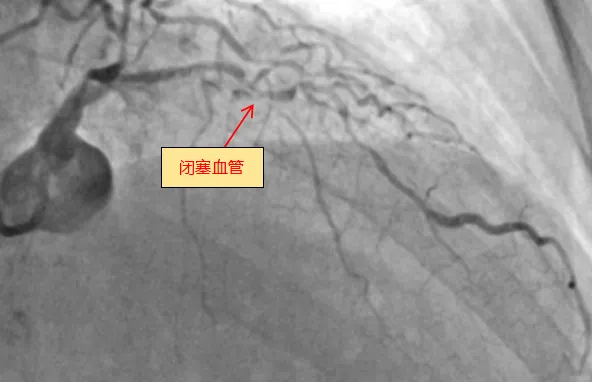

6月13日,捆绑调教 (简称捆绑调教 )心血管内科团队成功完成全新ROTAPRO™旋磨介入治疗系统上市后在广西的首次应用,为一名复杂高危严重钙化患者进行了精准冠脉介入治疗,顺利开通闭塞的冠脉血管并完成支架植入。71岁的梁阿姨(化名)去年外院冠脉造影诊断为冠心病,三支血管严重狭窄,于右冠植入一枚支架,前降支严重钙化病变尝试开通失败。近几个月来,她反复出现胸痛症状...